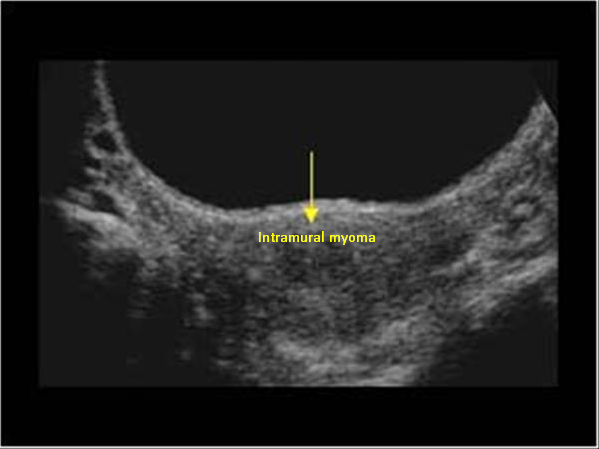

Myoma patients presented to the gynecology clinic due to complaints of prolonged menstrual bleeding and dysmenorrhea. During the transvaginal ultrasound (TVUS) examination, an intramural myoma was detected in 105 patients, submucous myoma in 35 patients, and intramural and submucous myoma detected in 60 patients (Figs. 1,2). Ovarian endometriosis was present in 105 of these patients. These patients were operated on by gynecologists. Pathology results were compatible with leiomyoma uteri (Fig. 3). The hospital stay was for 2 days. In the postoperative period, surgical site infection developed in 6 patients and hematoma at the incision line in 3 patients. Hematoma drainage was performed in only 1 patient. Surgical site infection resolved with antibiotic treatment. During the follow-up period, abdominal wall endometrioma developed only in the patient who underwent intervention due to myomectomy + ectopic pregnancy at the same time (0.5%). Characteristics of the 3 groups are shown in Tables 3,4.

Fig. 1. Transvaginal ultrasonography of intramural myoma.